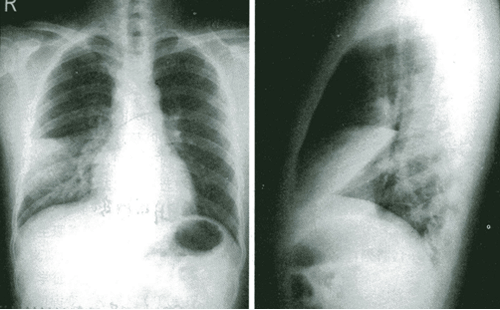

二、心包积液

1.后前位可见心缘正常弧段消失,心影向两侧扩大,呈“普大”型或球形。

2.多数病例肺血管纹理正常,部分病例可伴有不同程度的上腔静脉扩张。

3.心缘搏动减弱或消失,而心包外的主动脉搏动正常。(透视)